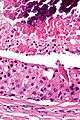

| Low magnification micrograph of a salivary duct carcinoma with characteristic comedonecrosis (left of image) adjacent to normal parotid gland (right of image). H&E stain. | |

Very low mag.

Intermed. mag.

Very high mag.